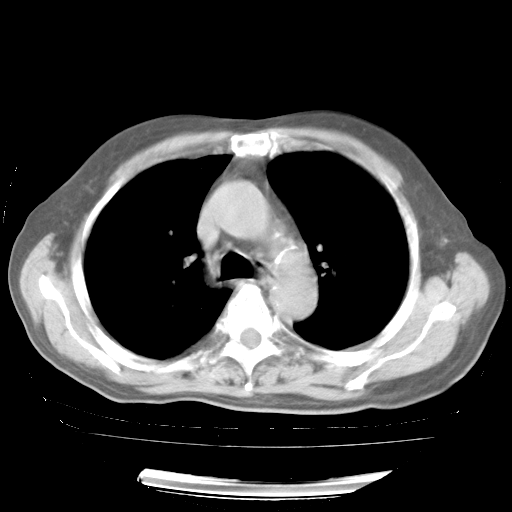

4月28日肺部CT——再次出现类似去年5月9日——透光度降低,“间质性”改变。

4月28日肺部CT——再次出现类似去年5月9日——磨玻璃样、间有“粟粒样”改变。

4月28日肺部CT